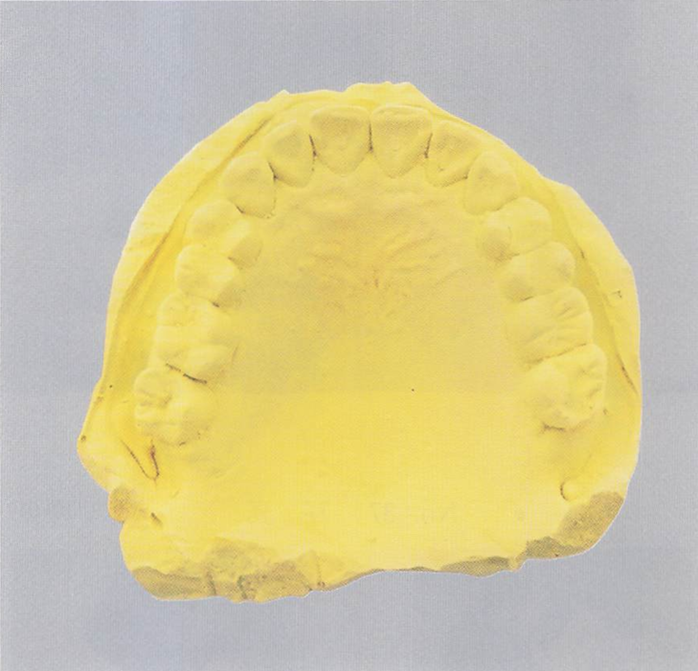

午前-92

印象体から撤去した直後の模型の写真を別に示す。 感染対策として模型に行うのはどれか。1つ選べ。

a.EOG滅菌を実施

b.10%ホルマリン溶液に浸漬

c.2%グルタラール溶液で払拭

d.アルコール系消毒薬を噴霧して密閉

解答を見る

d